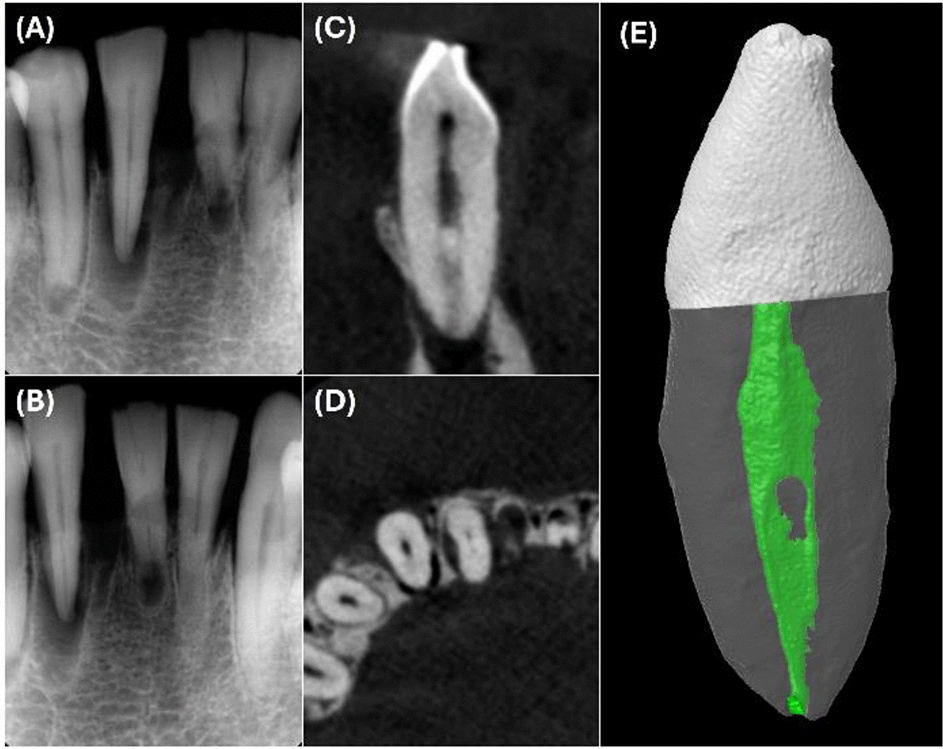

Assessment of unfilled and filled canals in mandibular incisors: comparison between periapical radiography and cone-beam computed tomography

The aim is to compare periapical radiography and cone-beam computed tomography (CBCT) in assessing the number of root cana...